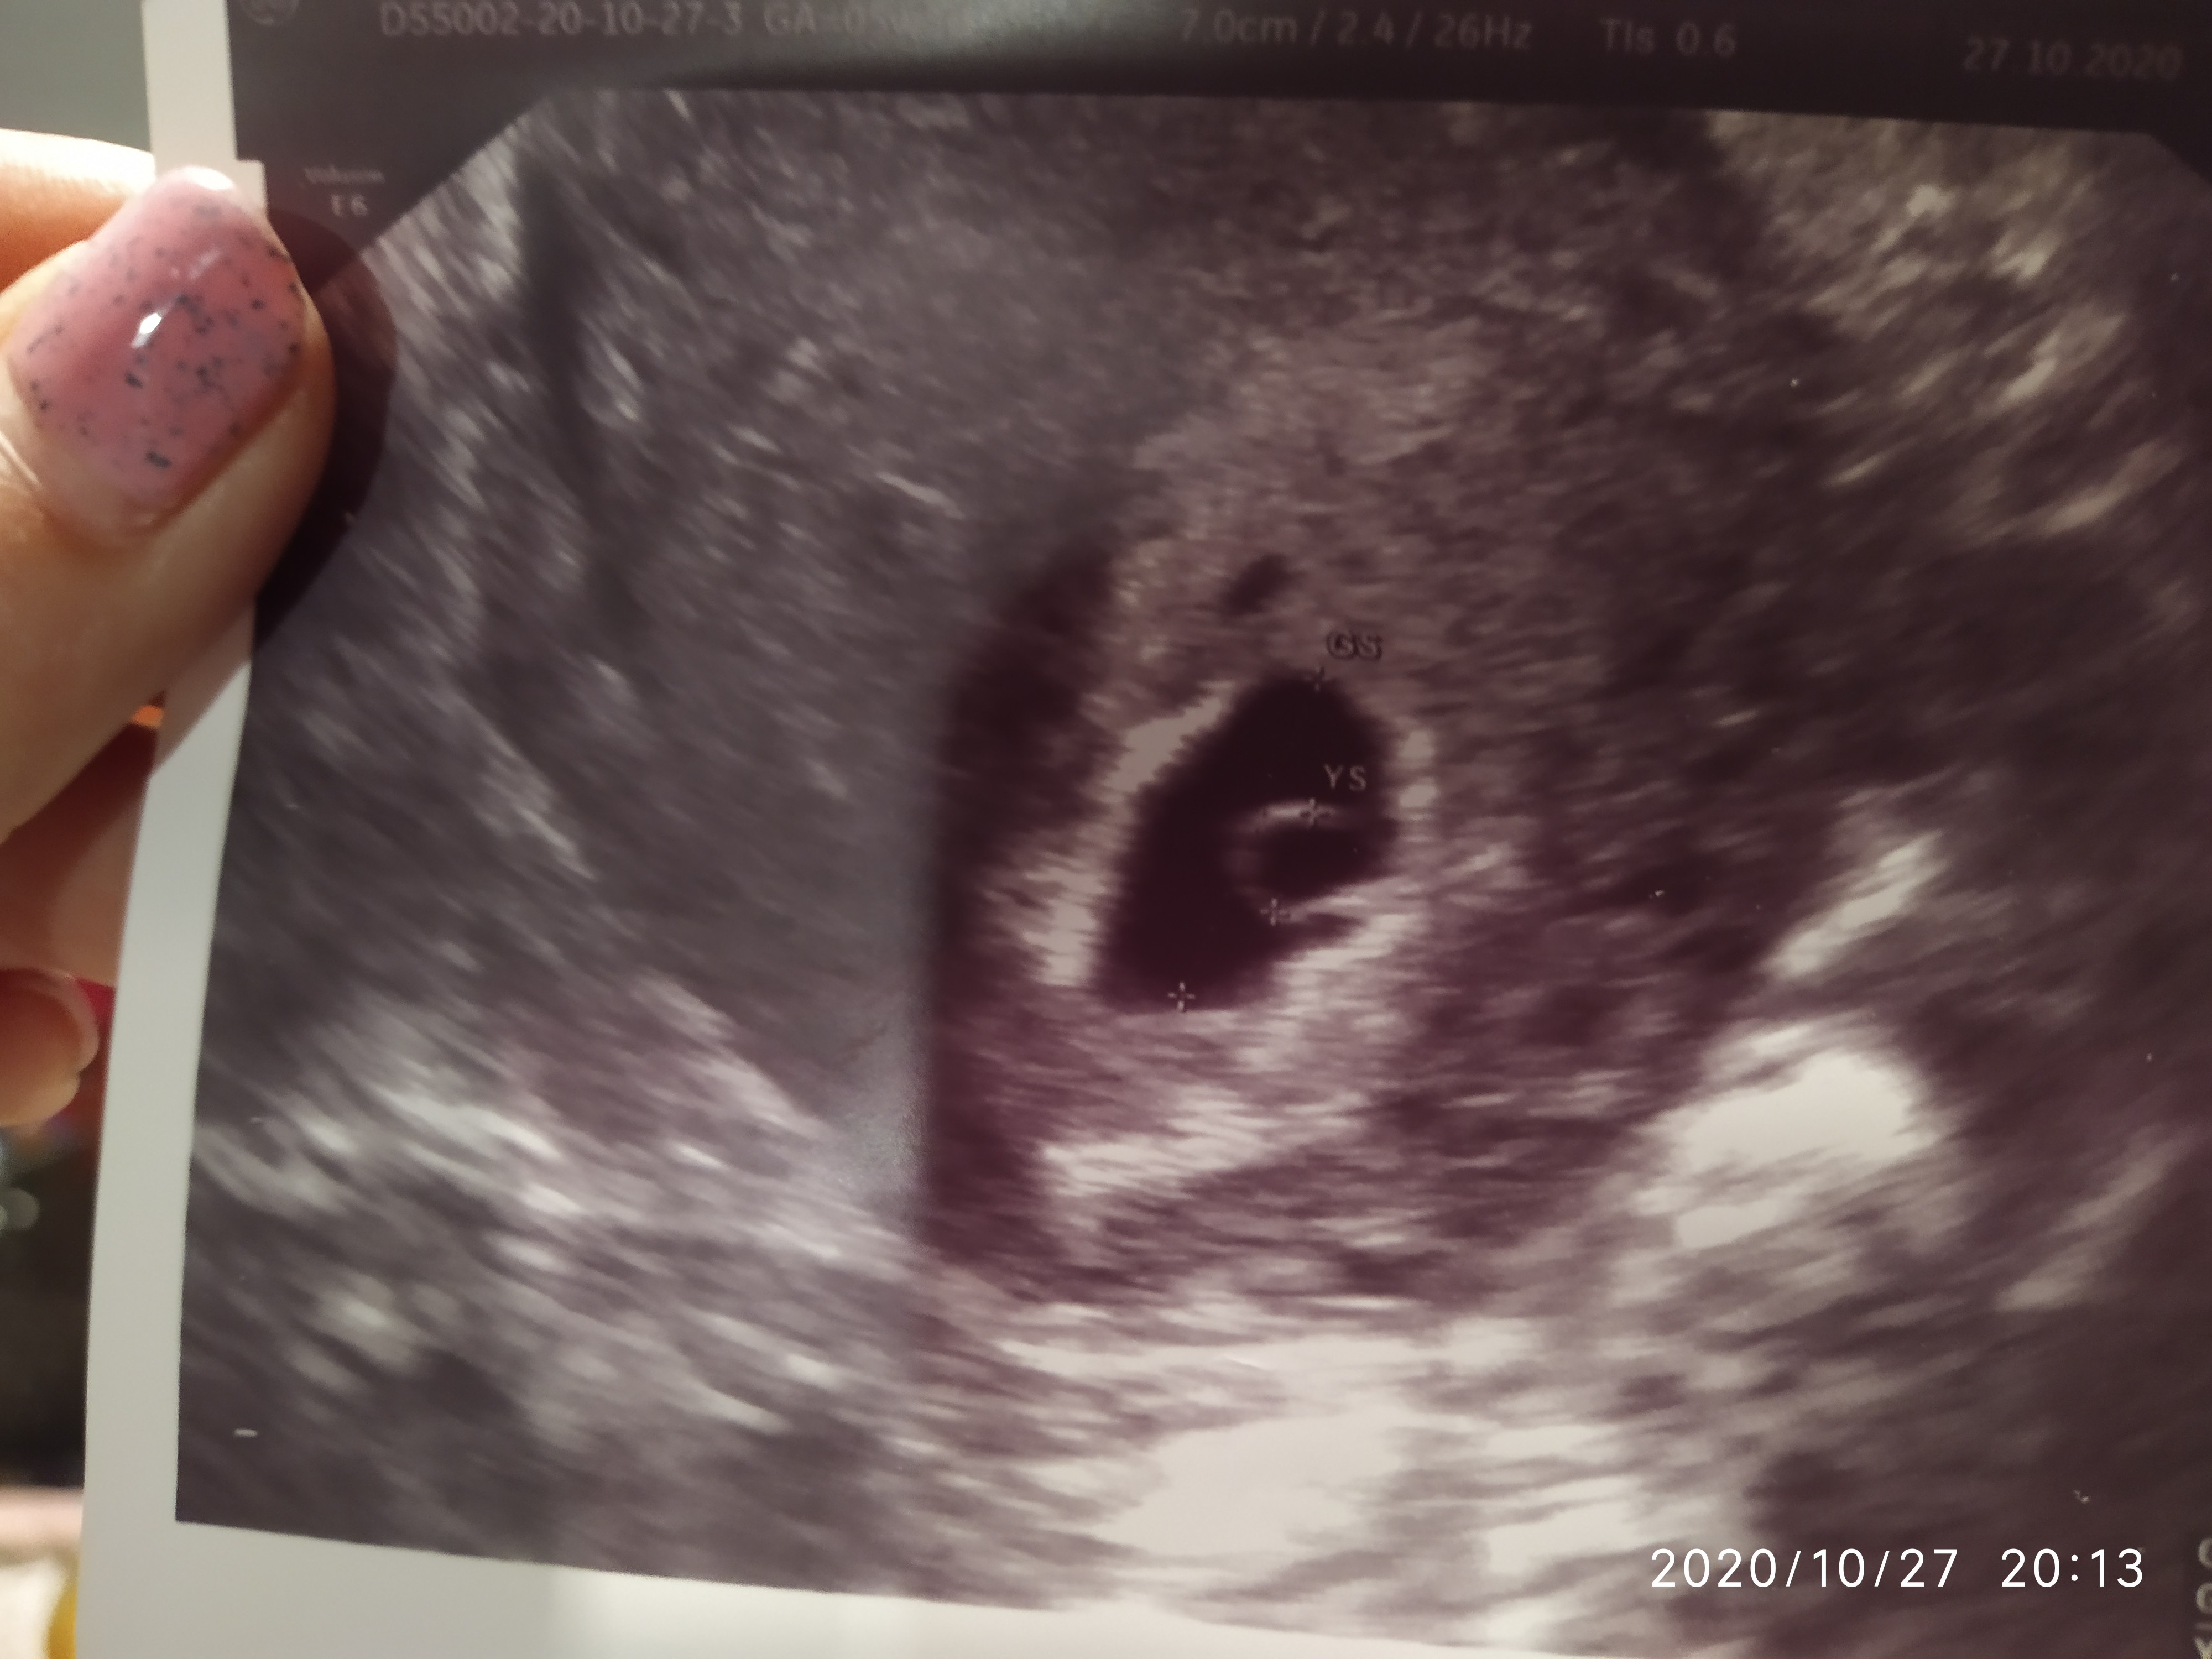

Ja tylko szybko, u mnie jest pęcherzyk w macicy, choć baaaaardzo długo szukany. Ale jest. Mam nadzieję że będzie dobrze

Nie kazałam lekarzowi włączać, bo już nie raz słyszałam, żeby lepiej nie męczyć. Na USG pokazało 6+1, ale lekarz mierzył już po skończeniu badania, trochę od niechcenia. W trakcie badania widziałam z innej perspektywy, że maleństwo jest trochę większe, i pewnie nie zmierzył w tym momencie, w którym powinien, ale cóż. Wiem, brzmi to jakbym była mądrzejsza od lekarza, ale ja mu po prostu nie ufam, bo bagatelizuje wiele spraw

Według OM 8+4, ale raczej jest to 7+4, ciężko stwierdzić, więc ciąża troszkę młodsza.